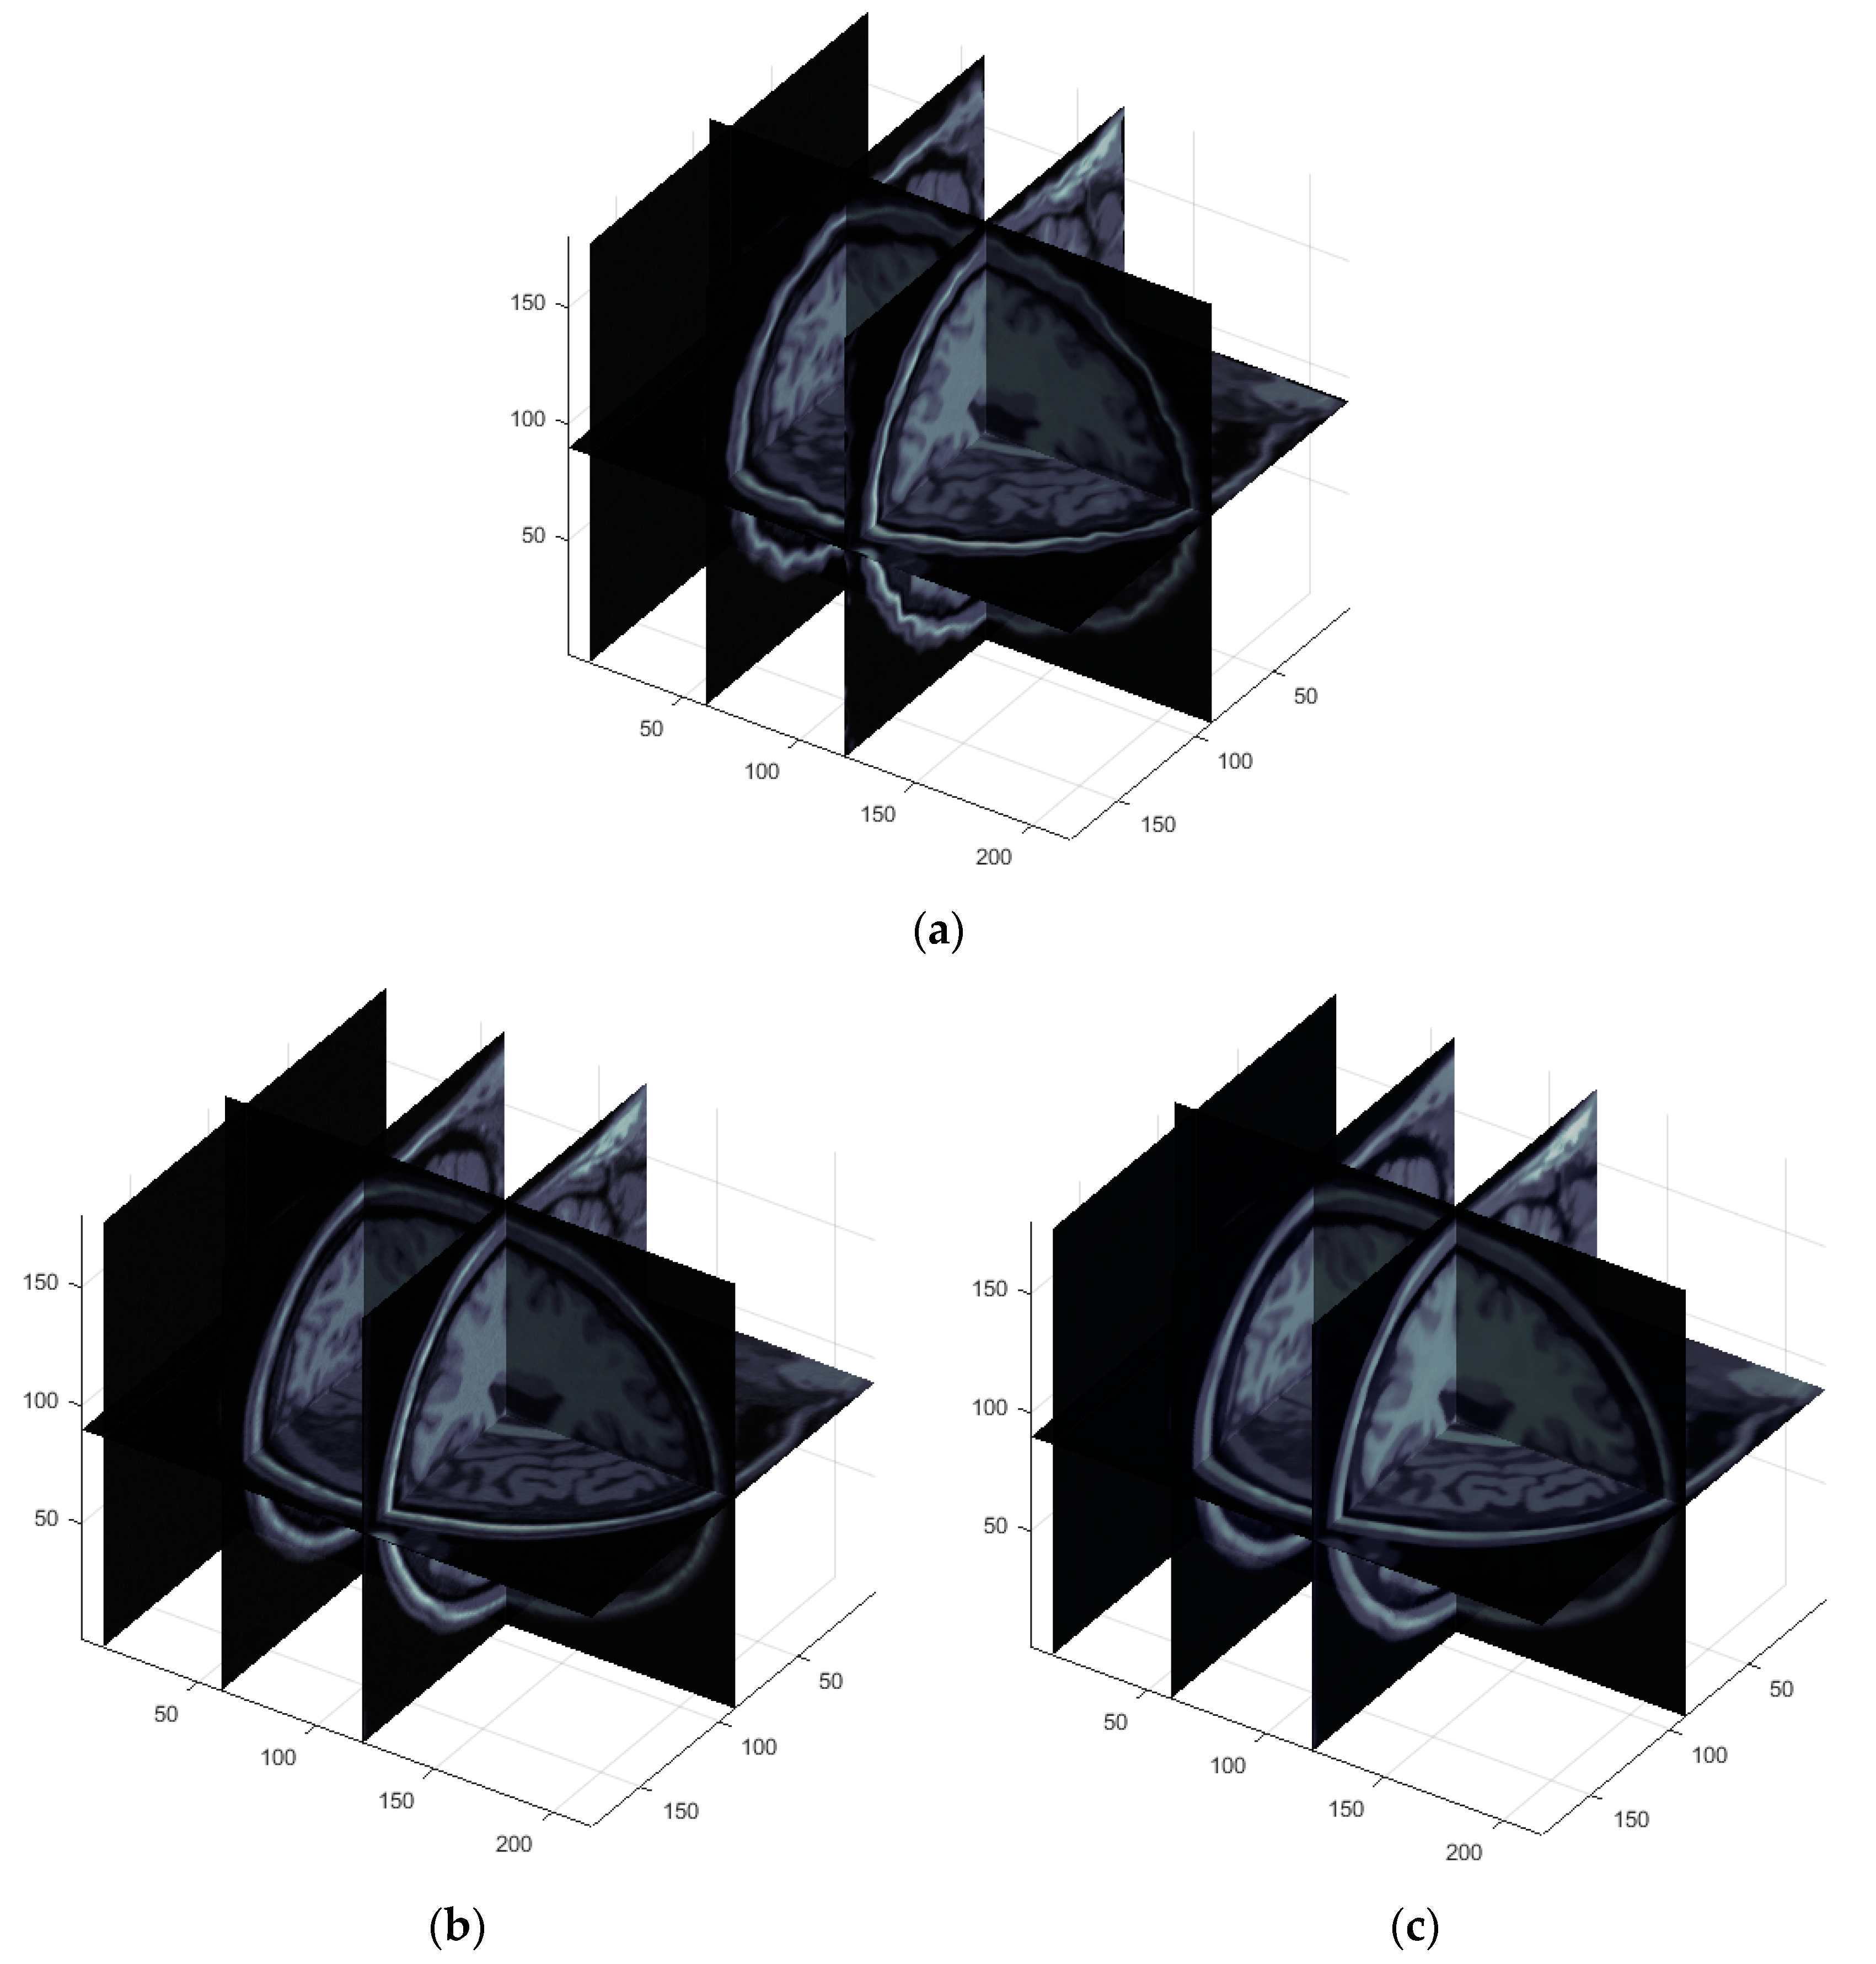

3.2.2. 3D Volume Registration